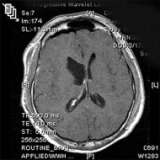

- Magnetic resonance imaging (MRI) is the preferred diagnostic tool, although the diagnosis should be confirmed by microscopic examination of the tumor from a biopsy.

- Sometimes, ependymomas are best removed with the aid of intra-operative MRI, allowing the most complete, safest surgery possible.

This post-operative MRI (above) confirms image-complete removal of the tumor. - Radiation Therapy